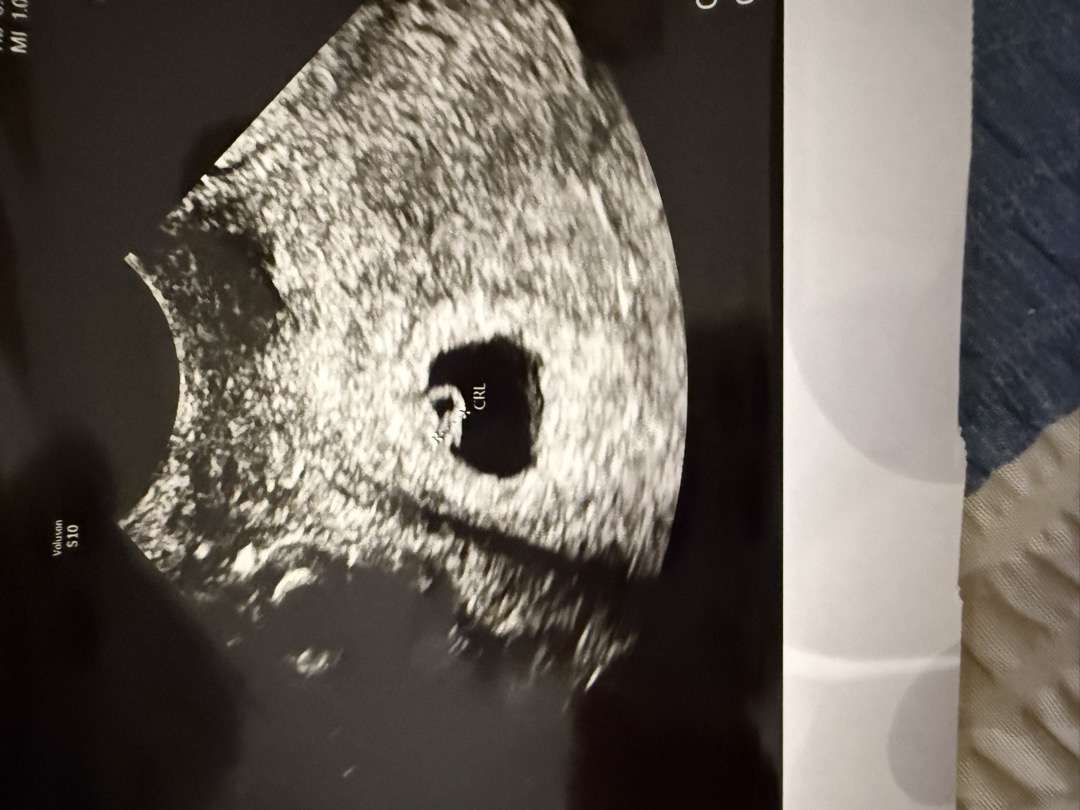

6주 1일차에 심소는 못듣고 깜빡임만 보고 왔어요 일주일 뒤에 다시 가니 심소 들을 수 있었고요!

오늘 초음파 보는 날이었습니다 난황이랑 아기집은 보이는데 심장깜빡임이없어서 3일 뒤에 오라고 하네요. 늦게 들으신분들 있을까요?ㅠㅠ